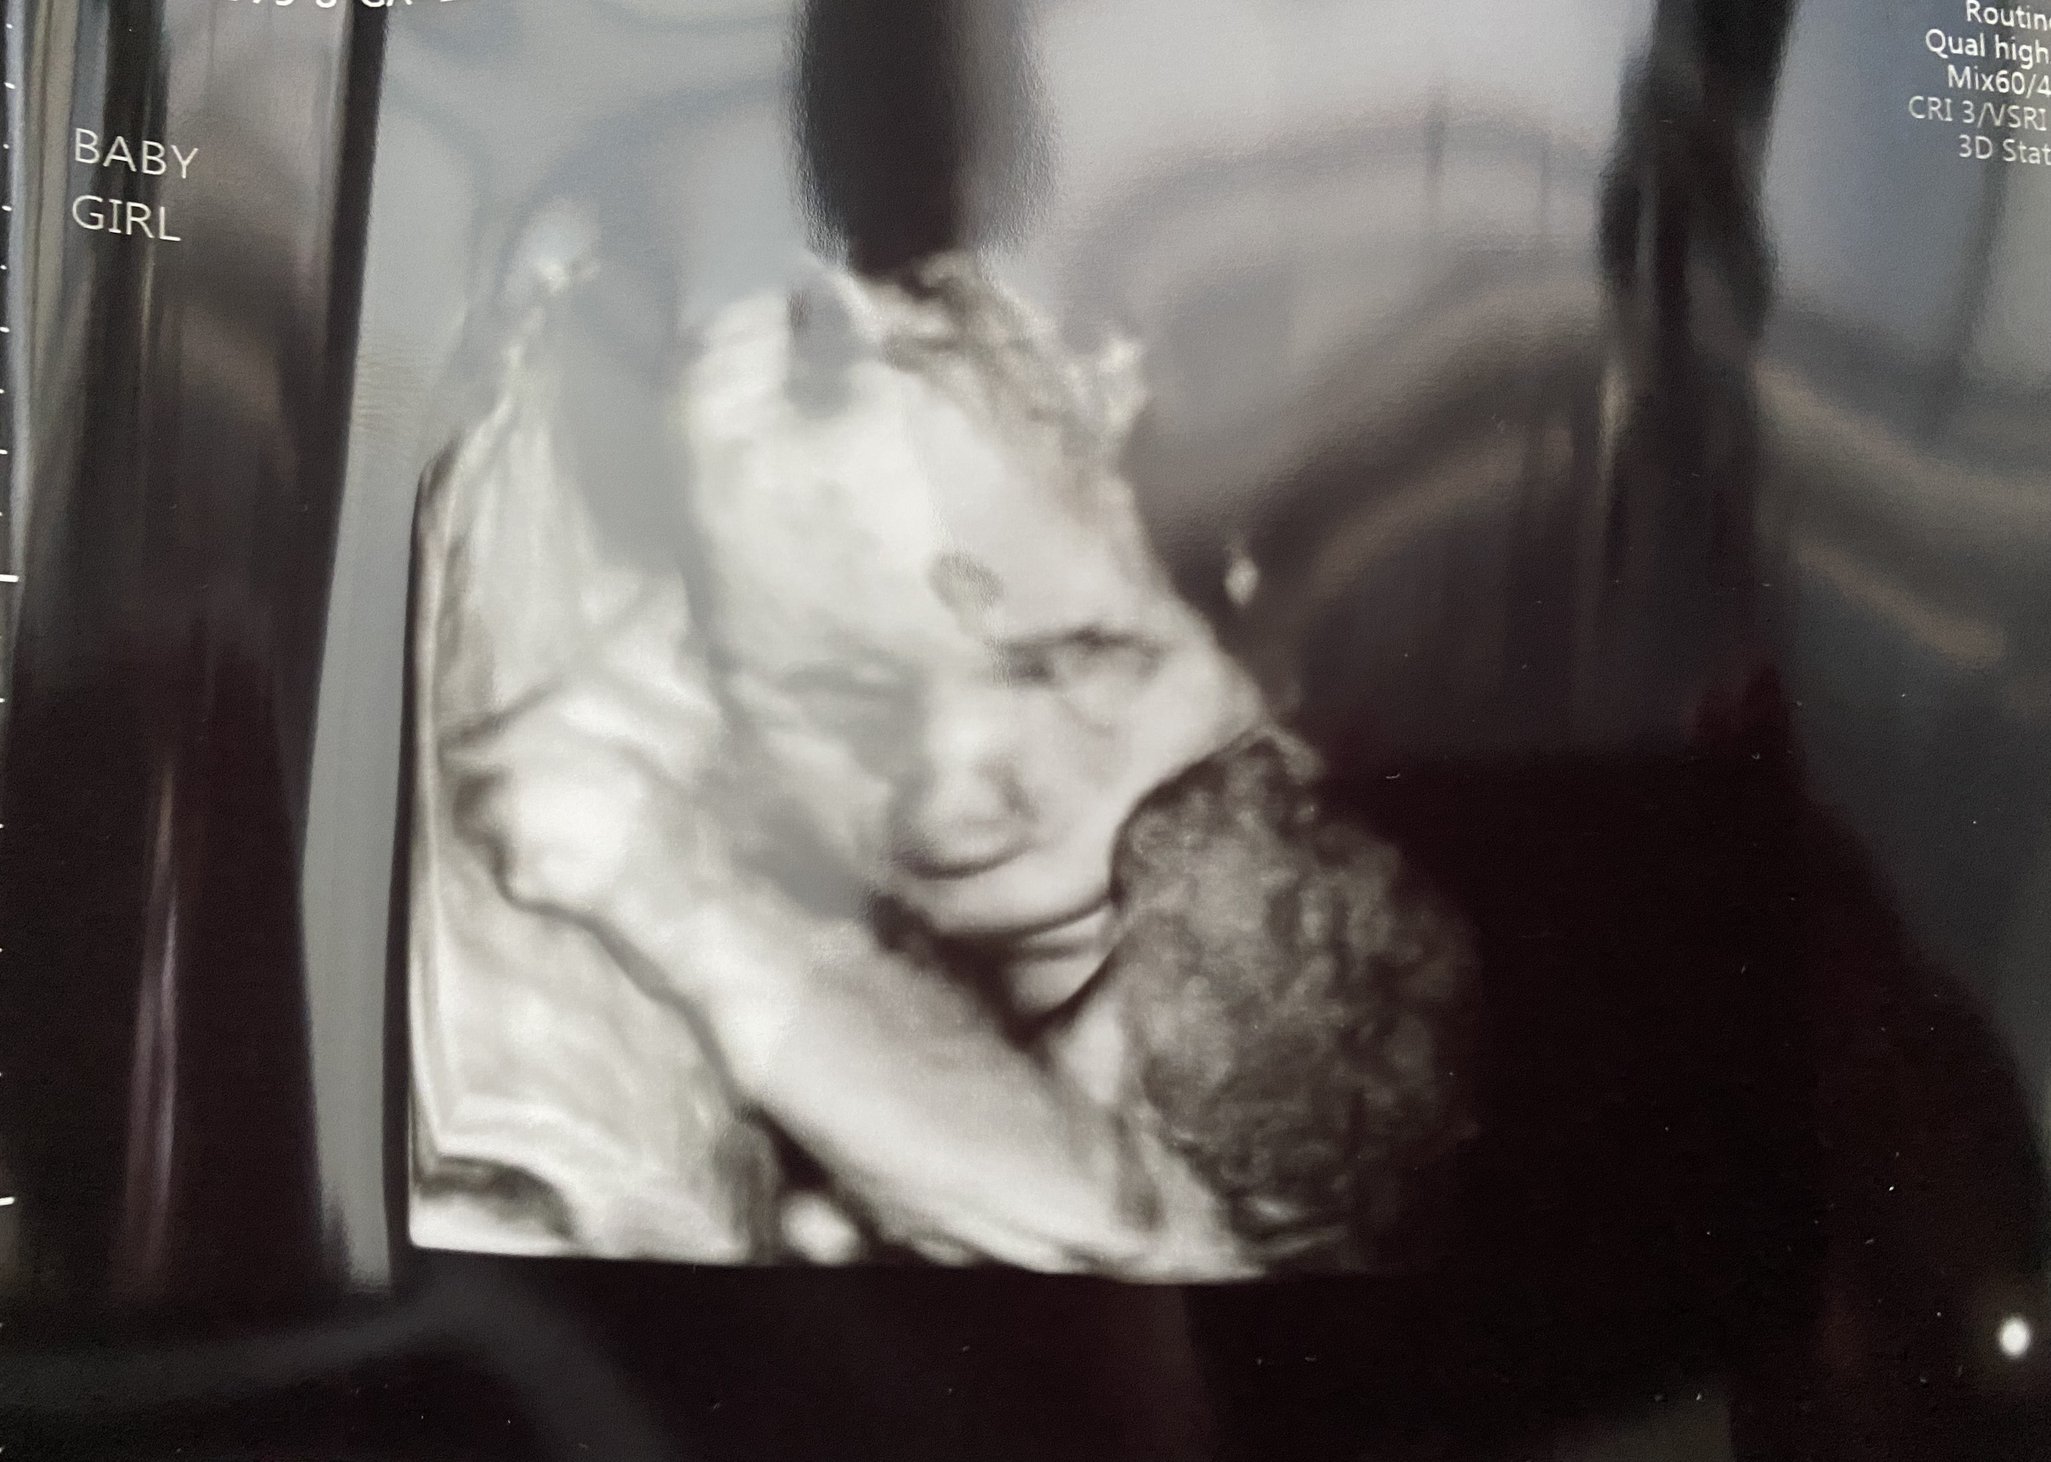

We had our follow up scan today to get the remaining pictures of baby girl's heart - all looks great, thank goodness! She's sucking her thumb here. She was still very active OR curled up in a ball and didn't want to move. Stubborn like her mama.